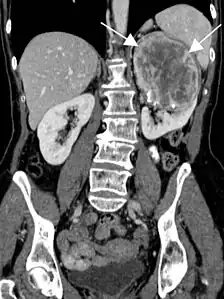

- Tumeur fibreuse solitaire du rein

Aspect tomodensitométrique. La tumeur est repérée par les flèches[46].

En tomodensitométrie[20],[31], quelle que soit la localisation, une tumeur fibreuse solitaire apparaît comme une masse tissulaire ovoïde ou lobulée, bien délimitée, refoulant les structures voisines sans les envahir. Elle se rehausse fortement après injection de produit de contraste. Les tumeurs de petite taille sont homogènes, mais les plus volumineuses présentent des plages hétérogènes de nécrose et d'hémorragie intra-tumorale. Il n'y a pas habituellement de calcifications et, lorsqu'elles sont présentes, elles sont de petite taille[31]. Les tumeurs malignes peuvent se présenter accompagnées de nodules pulmonaires métastatiques, et tendent à être plus volumineuses et plus hétérogènes[42].

L'imagerie par résonance magnétique permet une exploration complémentaire dans certaines localisations. Elle est surtout réalisée pour les tumeurs du système nerveux central[8],[12],[43], du foie et du pelvis[31],[41]. Elle évalue mieux les différences de densité intra-tumorale et permet d'affirmer l'absence d'envahissement des tissus mous et des structures osseuses voisines[20]. Les tumeurs fibreuses solitaires ont un aspect d'isosignal en séquence T1 et d'hypersignal en T2, et se rehaussent après l'injection de gadolinium[31]. Cependant, dans le système nerveux central, elles ne présentent pas de critères caractéristiques permettant de poser un diagnostic de manière uniquement radiologique[12] et, en pré-opératoire, sont souvent confondues avec un méningiome[43].